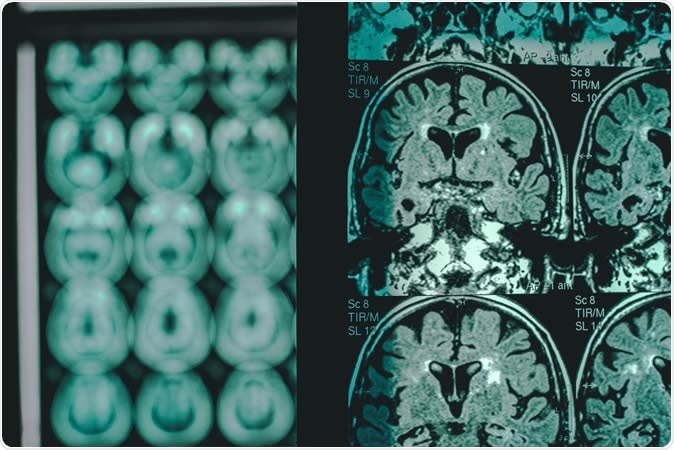

Alzheimer

Alzheimer's disease on MRI. Image Credit: Atthapon Raksthaput / Shutterstock